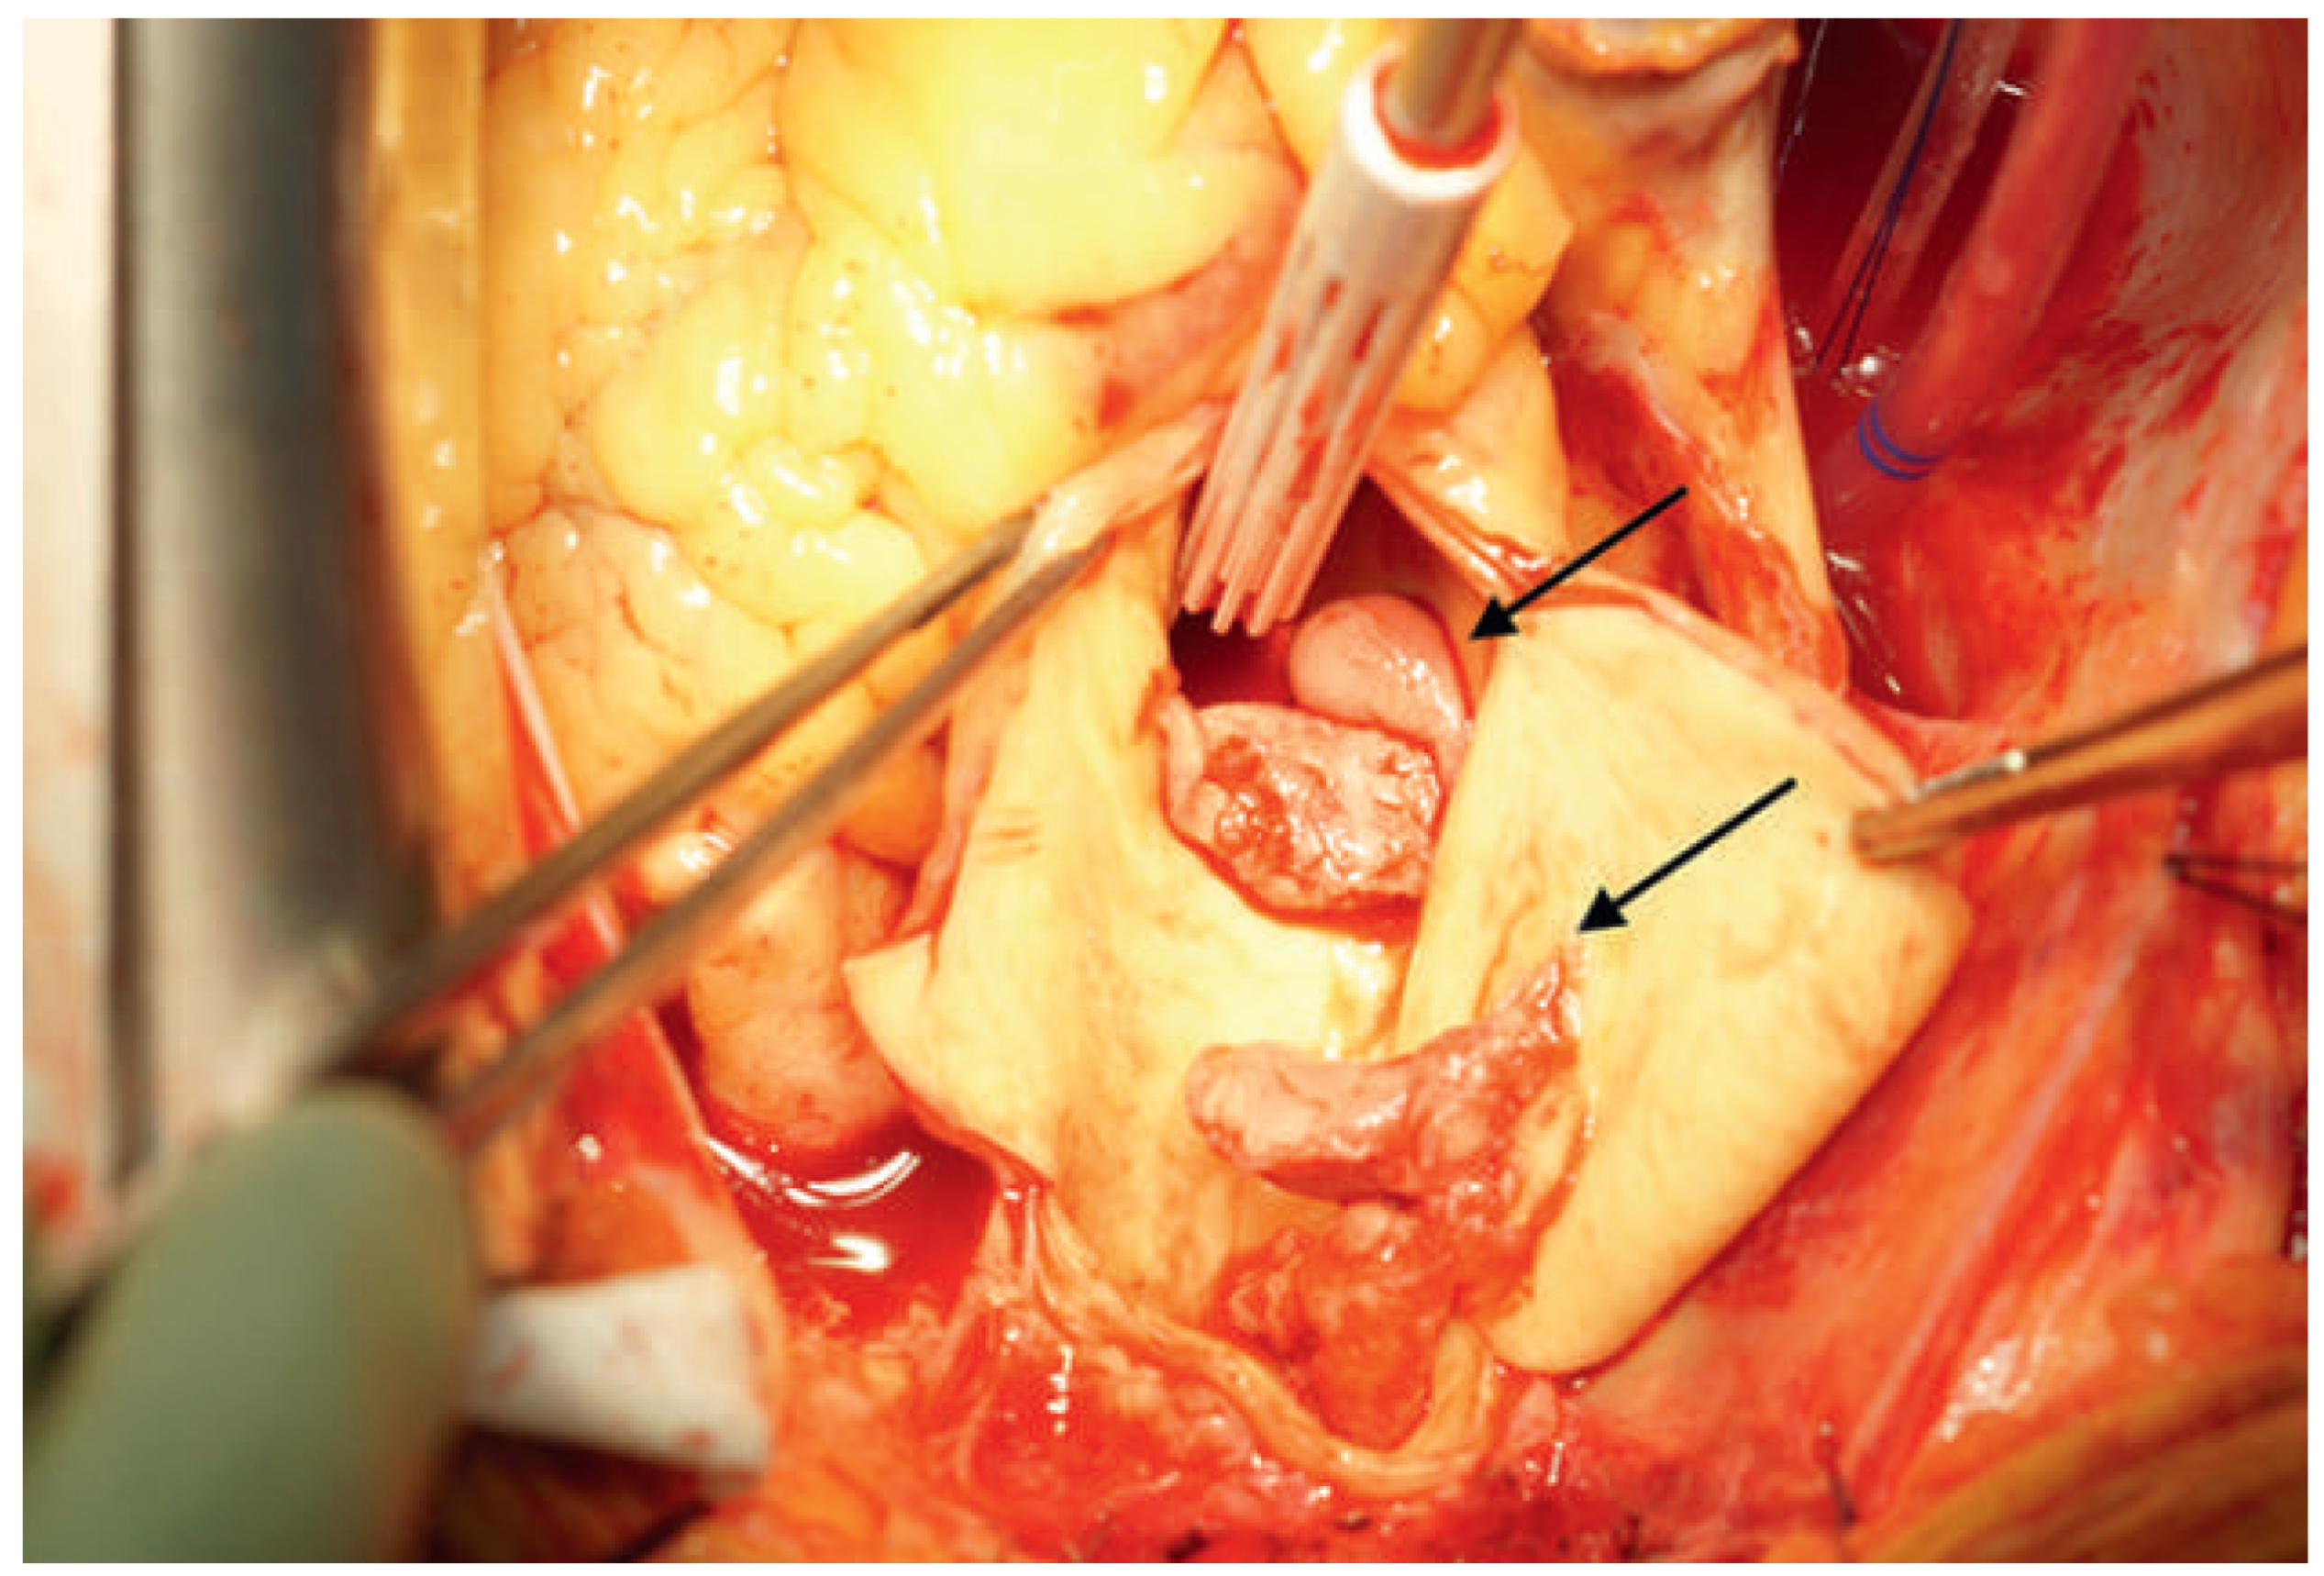

To avoid any further thromboembolic events, we decided to submit the patient to surgery and performed supracoronary ascending and hemiarch replacement in moderate hypothermic circulatory arrest; bypass grafting to the circumflex artery was not possible owing to a completely thrombosed vessel. The excised aortic segment showed three mobile rubbery structures, adherent to the aortic wall, one at the large curvature proximal to the brachiocephalic artery and two at the level of the sino-tubular junction right above the left coronary ostia (Figure 3 and Figure 4). Histological analysis revealed layered thrombi adherent to an aortic wall with mild atherosclerotic changes. There was no evidence of malignancy.

Figure 3. Intraoperative view: thrombotic material attached to the aortic wall (arrows).